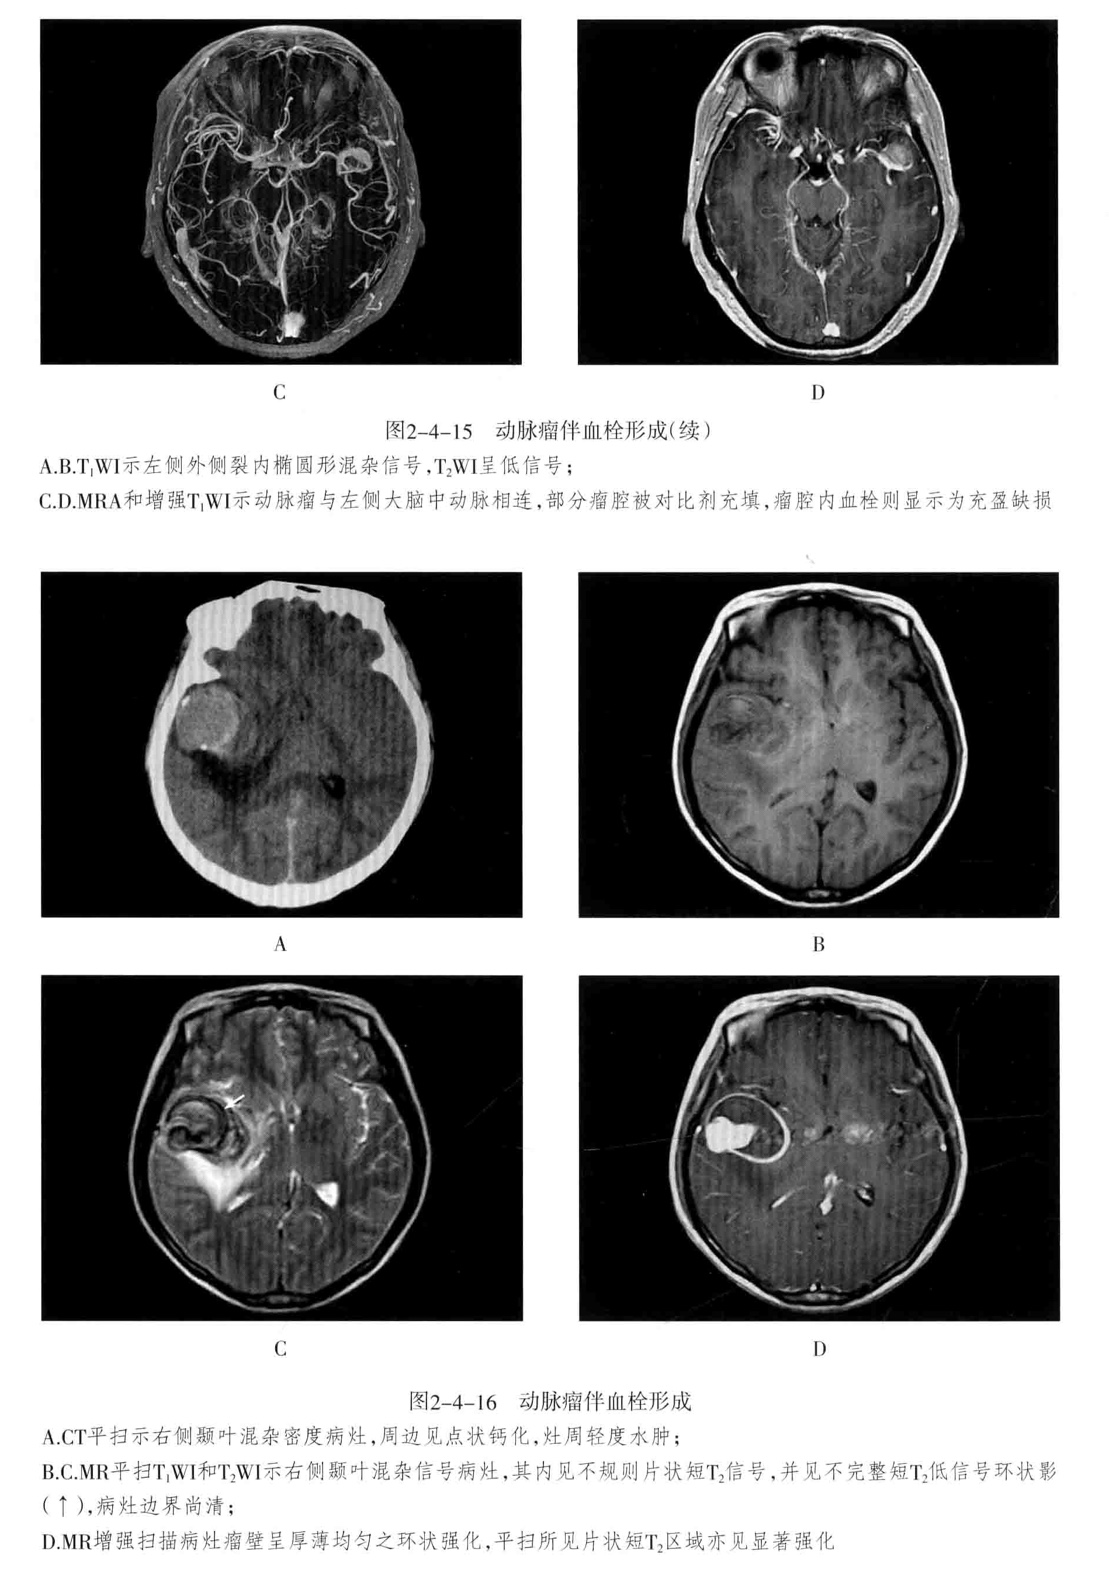

Galen静脉瘤是由于动-静脉短路,大量血流进入大脑大静脉,造成该静脉瘤样扩张所致。多见于儿童,特别是婴幼儿。典型的Galen静脉瘤包括明显扩张的Galen静脉和扩大迂曲的引流静脉。因动静脉短路造成盗血现象,可引起相应区域脑缺血。

Galen发生于Galen静脉区的特定部位,较大的Galen静脉瘤压迫中脑,导致中脑导水管闭塞,引发梗阻性脑积水。

脑血管造影、MRV/A:可直接显示扩张的瘤体,同时可见扩张的颈动脉或椎动脉分支直接与Galen静脉短路。CTA可见扩张的瘤体、供血动脉、引流静脉及扩张的静脉窦。

CT平扫:大脑大静脉区可见边界清楚的类圆形、三角形的高密度影,密度均匀,边缘常可见点状线状钙化。可见三脑室及其以上脑室系统积水,增强后均匀强化,有时可显示增粗的供血动脉和引流静脉及扩张的静脉窦。

MRI表现:是确诊Galen静脉瘤最好的方法;大脑大静脉区边界清楚的类圆形或三角形的信号不均的病灶。增强呈血管样明显强化,血流瘀滞表现为T1WI等或低信号、T2WI稍高信号。